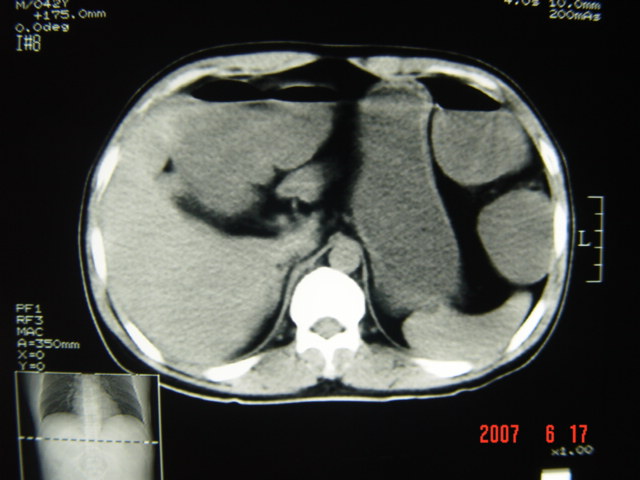

[br][br]以下是引用lkc8963在2007-6-17 13:32:00的发言:[br]完全支持邓主任意见:降/乙交界部占位性病变伴不全梗阻.做个增强或者be可能更好.